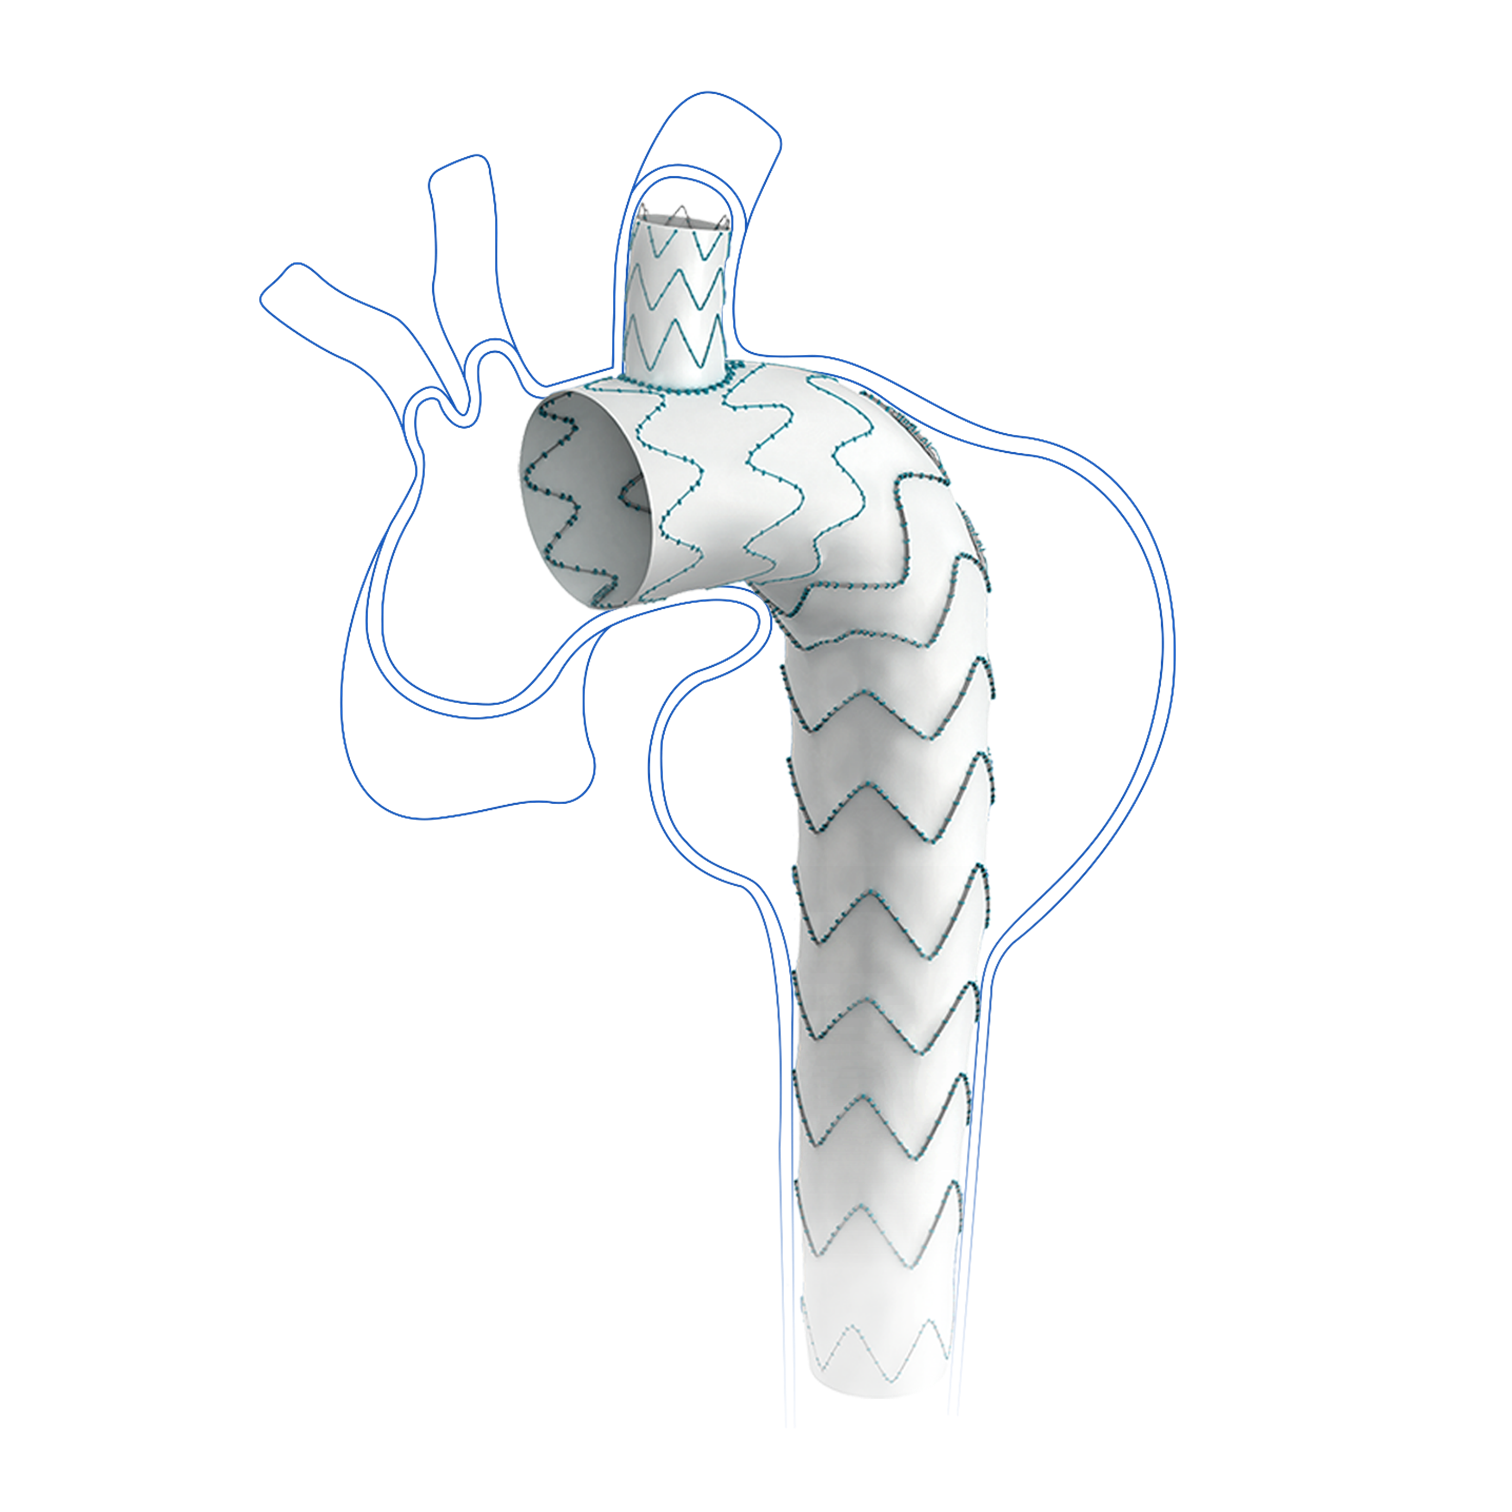

Cratos™ thoracic branch stent graft system is indicated for the treatment of thoracic aortic dissection involving aortic arch pathologies, enabling simultaneous endovascular repair of the aorta and reconstruction of supra-aortic branch arteries.

Cratos™ thoracic branch stent graft system is indicated for the treatment of thoracic aortic dissection involving aortic arch pathologies, enabling simultaneous endovascular repair of the aorta and reconstruction of supra-aortic branch arteries.